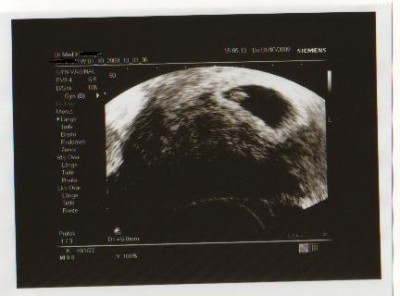

So jetzt weiß ich dass sich mein zweites Herzchen bis jetzt gut entwickelt. Das Herzchen hat fleißig geblinkt und Krümmel ist ca. 6mm gross, das mit 5mm vor 2 Tagen war nicht gemessen, das war nur die Schätzung des Kiwudoc´s aber heute wurde Kleines gemessen. :wink:

Gemessen ist gemessen. :wink:

Hier ein Foto von heute.

Dateianhänge

SSW 6+6.jpg

22.08-6+6 2.US-